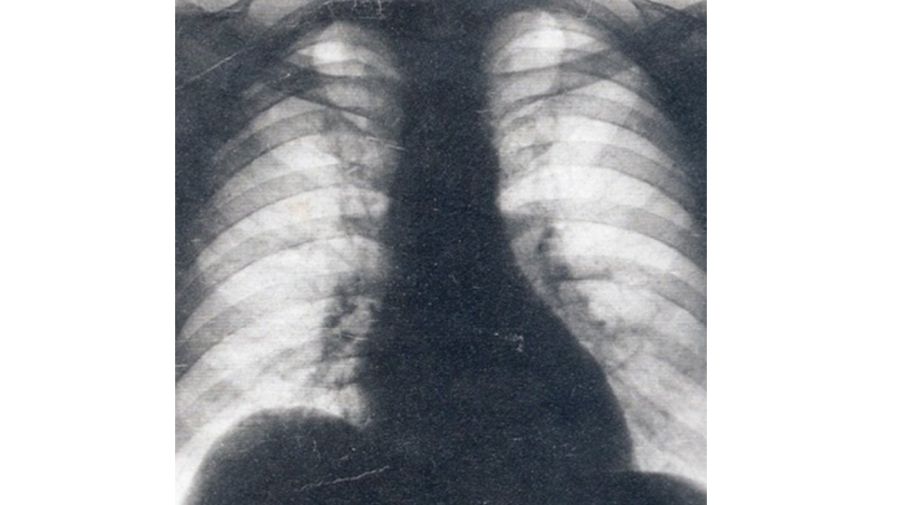

Consignó por escrito: “A raíz de un examen radiográfico se comprobó que el señor coronel Don Juan Domingo Perón presenta una elevación cupiliforme del hemidiafragma derecho cuyo probable origen tumoral sea imprescindible e impostergable dilucidarlo por el examen clínico y de laboratorio en un ambiente hospitalario (…). El clima húmedo de su actual alojamiento le puede resultar sumamente desfavorable”.

Horas después, Mazza se reunió con el presidente Farrell y le mostró las "pruebas". Entre ellas había una radiografía, que no pertenecía a Perón: había sido extraída de la historia clínica de otro paciente en el Hospital Militar.